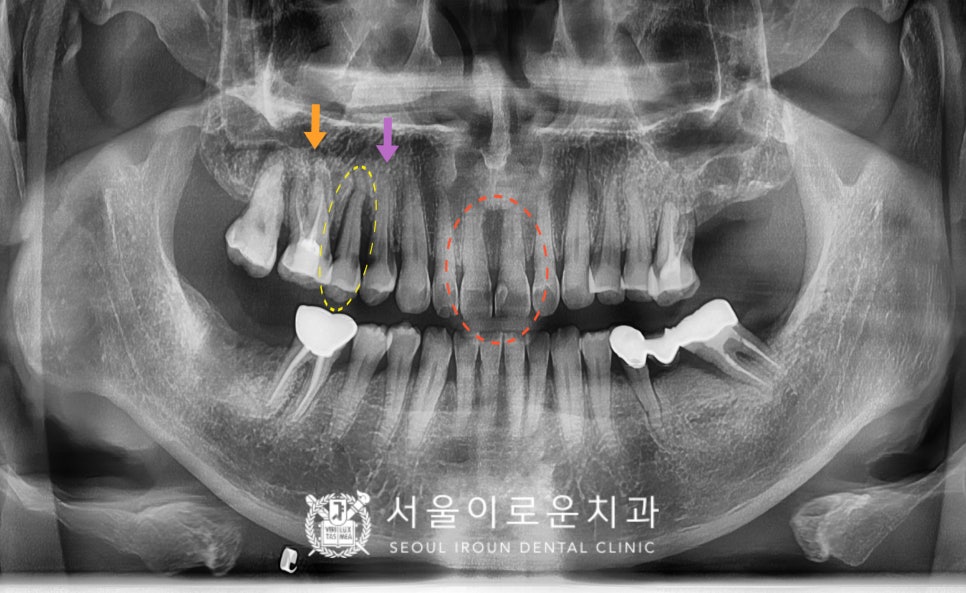

노란색 동그라미의

오른쪽 위턱 두 번째 작은 어금니(#15)의

뿌리 주변으로 잇몸뼈가

많이 흡수되어 있었으며,

충치도 심한 것을 확인할 수 있었습니다.

이 경우 살려 쓰기 어려울 것으로 판단되어

안타깝지만 발치가 필요한

상황이었습니다.

그리고 보라색 화살표의

오른쪽 위턱 첫 번째 작은 어금니(#14) 또한

통.증을 호소하셨는데요.

충치가 치아의 허리 부분에 해당하는

치경부 깊이 진행되어 있어

신경치료 후 크라운 치료가 필요하였습니다.

또한 주황색 화살표의

오른쪽 위턱 첫 번째 큰 어금니(#16)는

예전에 신경치료까지만 진행이 되어있고

크라운 수복을 하지 않은 상태였는데요.

그렇다 보니 레진 경계부에

이차우식이 진행되어

크라운 치료가 필요하였습니다.

그리고 마지막으로

환.자분께서 말씀하셨던

빨간색 동그라미의 앞니(#11,12)

충치 부분은

그냥 육안으로 보기에도

두 개의 치아 사이에

까맣게 충치가 생긴 것을

확인할 수 있었는데요.

다행히 충치가 신경까지

진행이 되지 않은 상태라

신경치료는 하지 않아도 되는 상황이었지만

충치가 있는 치아머리 일부를 삭제하고 나면

잔존 치질량이 얼마 되지 않아

치아가 약해지기 때문에

충치 제거 후 레진으로 보강한 뒤

크라운 치료를 계획하였습니다.